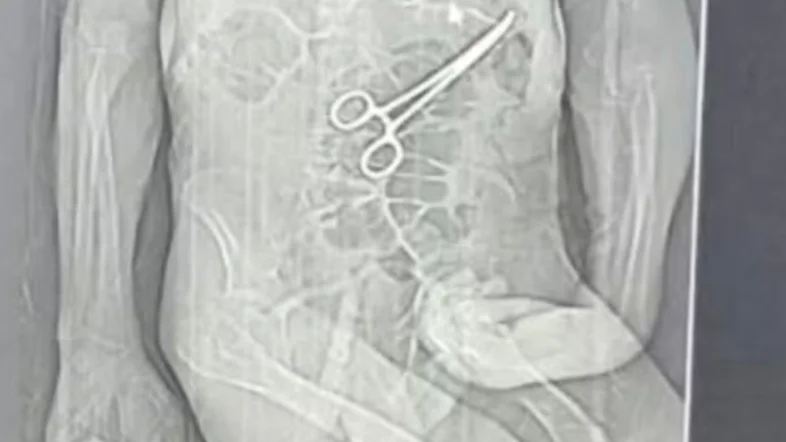

Homem morre na véspera do Natal e família diz que pinça foi deixada em seu corpo

O aposentado Manoel Cardoso de Brito, de 68 anos, morreu na véspera do Natal vítima de complicações decorrentes de duas cirurgias realizadas no Hospital Municipal de João Pinheiro, em Minas Gerais. A família acusa autoridades de erro médico. Segundo parentes do aposentado, uma pinça cirúrgica teria sido esquecida dentro de seu corpo durante o primeiro procedimento cirúrgico, realizado no início do mês.

A Secretaria Municipal de Saúde de João Pinheiro confirmou, em nota, que houve “a retirada de um corpo estranho durante a (segunda) cirurgia do paciente”, mas afirmou que Brito estava em estado muito grave, com várias comorbidades. Informou ainda que reforçou protocolos de segurança e abriu sindicância para apurar o caso.

Logo após a morte do aposentado, uma rádio local teve acesso a um exame de tomografia que indicaria a presença de um instrumento cirúrgico dentro do corpo do paciente. A família informou que acompanha as apurações e vai requisitar os prontuários, laudos e exames clínicos feitos no hospital.

Nota divulgada pelo hospital confirma a retirada de “um corpo estranho”, mas ressalta que, “durante o segundo procedimento não foi constatada perfuração da alça intestinal e as suturas do procedimento anterior encontravam-se íntegras. O procedimento foi realizado sem intercorrências adicionais. No dia seguinte, a família foi novamente informada sobre o procedimento realizado, bem como sobre a identificação e retirada do corpo estranho”.